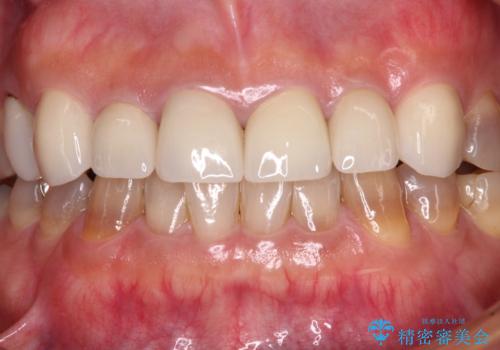

- 前歯のテトラサイクリンによる変色歯と、レジン充填の色の違いを気にして来院された患者様です。

患者様の希望により、前歯6歯をオールセラミッククラウンにて補綴することとしました。

長年前歯の色の違いに悩んでいらっしゃったようですが、仮歯に変えた時点で統一感のある白さとなり喜んで頂きました。

わずか1ヶ月の間にとても自然な仕上がりのセラミッククラウンが装着され、患者様には大変満足していただきました。